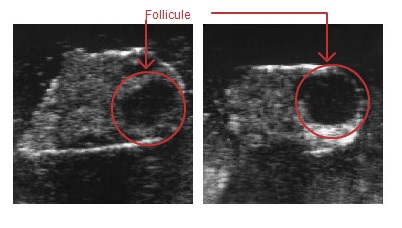

Ovaire: Préchaleurs

Le corps jaune (corpus luteum) s’est fortement résorbé sous l’influence de la prostaglandine F2alpha. Un follicule dominant (follicule de Graaf) croît. Il est lisse et rebondi (comme le verre d’une montre) et a un diamètre d’un bon centimètre.